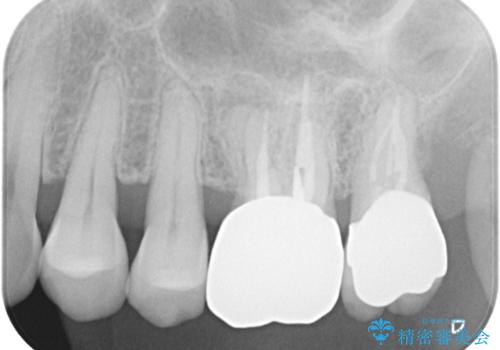

【根管治療】ズーンと痛い歯の治療。

- 奥歯付近がジーンと痛いことを主訴に来院されました。

左上7番の歯は、歯髄検査にて反応を示し、歯周ポケットはありませんでした。

親知らず抜歯を行い、痛みの変化や歯根吸収の有無を確認したのち、抜髄処置を行っています。

症状改善し、遠心の骨の回復も認めます。

バイオセラミックシーラーを使用して根管充填を行っています。